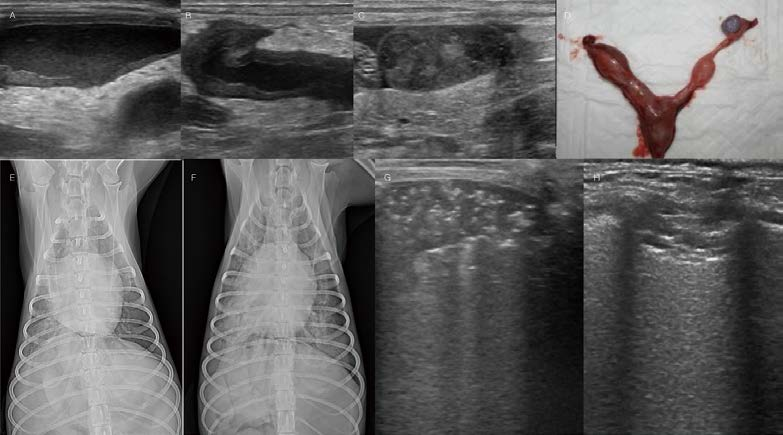

[대한수의사회지 24.png

전형적이지 않는 폐렴 환자 증례입니다. 11개월 4.3kg 중성화 수컷 Maltese가 식욕저하, 기력저하, 호흡곤란 증상으로 내원하였습니다. 약 15일 전 기침 증상으로 대증 치료를 받고 일시적 개선되었던 병력이 있었습니다. 흉부방사선 검사에서 폐 전반에 걸쳐 한계가 불명확한 연조직밀도의 작은 크기의 nodular lesions이 다수 관찰됩니다(A. B). 폐초음파 검사에서 폐엽 여러 군데에서 micro-consolidation(Tiny areas of sub-pleural consolidation)이 관찰됩니다(D, E, F). 이러한 소견은 다양한 감별 진단이 가능하며, Pneumonia(e.g., fungal pneumonia, eosinophilic pneumonia…), pulmonary thromboembolism, 종양의 전이 등을 고려할 수 있습니다. 환자는 추가적인 검사가 지시되어 CT 검사, Bronchoalveolar lavage를 실시하였습니다. CT 검사에서 기관지 주변 간질에서 nodular ground glass opacity가 폐엽 전반에 걸쳐 다수 관찰됩니다. 유의적인 Pulmonary thromboembolism 소견, 다른 부위의 종양성 변화는 확인되지 않았습니다. 환자는 PCR, 배양 등의 실험실학적 검사에서 Bacillus cereus 감염원이 확인되었습니다. 항생제 감수성 검사를 바탕으로 amoxicillin/clavulanic acid, enrofloxacin 처방을 통해 환자의 임상 증상, 흉부 방사선, 페초음파는 모두 개선되었습니다. 폐초음파는 작은 병변이라도 lung periphery에 있다면 엑스레이 검사보다 훨씬 더 잘 관찰됩니다. 병변의 양상으로 감별 진단 목록을 작성하고 환자의 검사 plan을 제시할 수 있습니다. 또한 치료 과정에서 병변이 잘 개선되는지 세밀하게 확인할 수 있습니다.

<※증례 ③>

전형적이지 않는 다른 폐렴 환자 증례입니다. 1살 5개월의 7.6kg 중성화 수컷 꼬똥 드 뚤레아가 기침 증상으로 내원하였습니다. 식욕 및 컨디션은 다소 양호한 편이었으나, 약 한달 반 동안 지속적인 기침 증상을 보였습니다. CBC에서 mild leukocytosis(CRP는 upper normal limit), moderate eosinophilia가 관찰됩니다. 기본 흉부방사선 검사에서 오른쪽 전엽 전반적으로 밀도 상승, bronchiectasis, gas bubbles(?) 소견이 관찰됩니다(A, B). 폐초음파 검사에서 오른쪽 전엽은 정상 폐구조가 소실되어 보이고, 바깥으로 bulging 종대되어 있습니다(J). 이러한 폐초음파 소견의 감별 진단으로는 폐종양, necrotizing pneumonia 등을 고려할 수 있습니다. 환자는 추가적인 검사가 지시되는 바, CT 검사 및 bronchoalveolar lavage를 실시하였습니다. CT 검사(C, D, E, F, G, H, I)에서 오른쪽 전엽으로 가는 bronchi의 severe tortuous dilation, mucoid impaction, pruning 소견이 관찰됩니다. 오른쪽 전엽에서 조영 증강되지 않는 일부 영역은 necrotic region 가능성도 고려할 수 있습니다. 폐초음파에서 폐구조가 소실되어 보인 주된 이유는 기관지가 mucoid impaction으로 tortuous하게 확장되어 있었기 때문으로 생각됩니다. Bronchoscopy에서 오른쪽 전엽 기관지 모두 농성 분비물로 완전히 채워져 관찰됩니다(K). Bronchoalveolar lavage 및 실험실학적 검사에서 모든 감염원성은 배제되었고, eosinophilic pneumonia로 확인되었습니다(L). 환자는 스테로이드 및 예방적 항생제 처방으로 인해 폐침윤은 대부분 개선되었습니다(초진 이후 3개월, M, N). 많이 개선되어 보이나, bronchiectasis 남아 있어, 폐렴 재발 가능성, 폐렴이 반복될 경우 폐엽절제술 가능성에 대해서도 고지하였습니다.